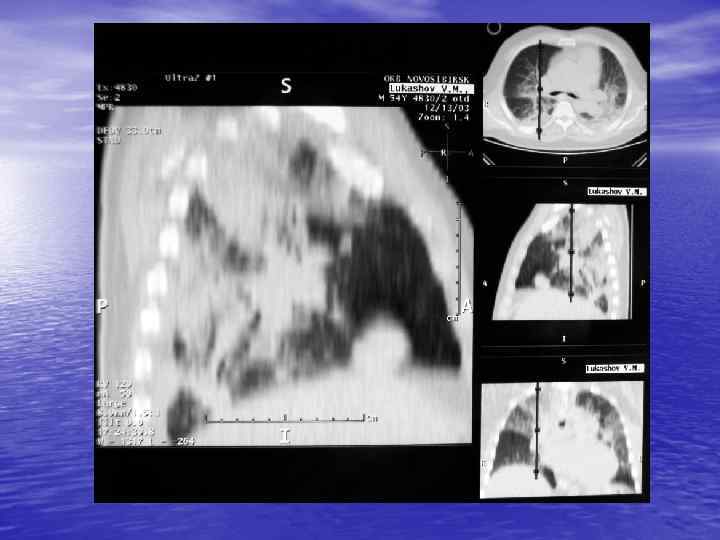

Спиральная КТ üНепрерывное вращение рентгеновской трубки вокруг объекта и непрерывное поступательное движение стола с пациентом üЗначительное ускорение процесса сканирования (15 -20 сек) üПринцип объемного сканирования, позволяющий получить непрерывный объем данных при исследовании выбранной анатомической области üШаг стола 0, 5 – 2 мм

Преимущества спиральной КТ: ü Возможность проведения исследования с болюсным ü ü ü ü ü контрастированием Высокая разрешающая способность; Высокая скорость исследования; Получение высококачественных изображений костных структур; Возможность обследования всего тела; Возможность проведения исследования больных под наркозом; Возможность детальной оценки состояния крупных и периферических сосудов в условиях искусственного контрастирования; Высокая информативность метода при черепномозговых травмах в остром периоде; Ранняя диагностика ишемических и геморрагических инсультов; Метод выбора для диагностики заболеваний легких; Планирование лучевой терапии.